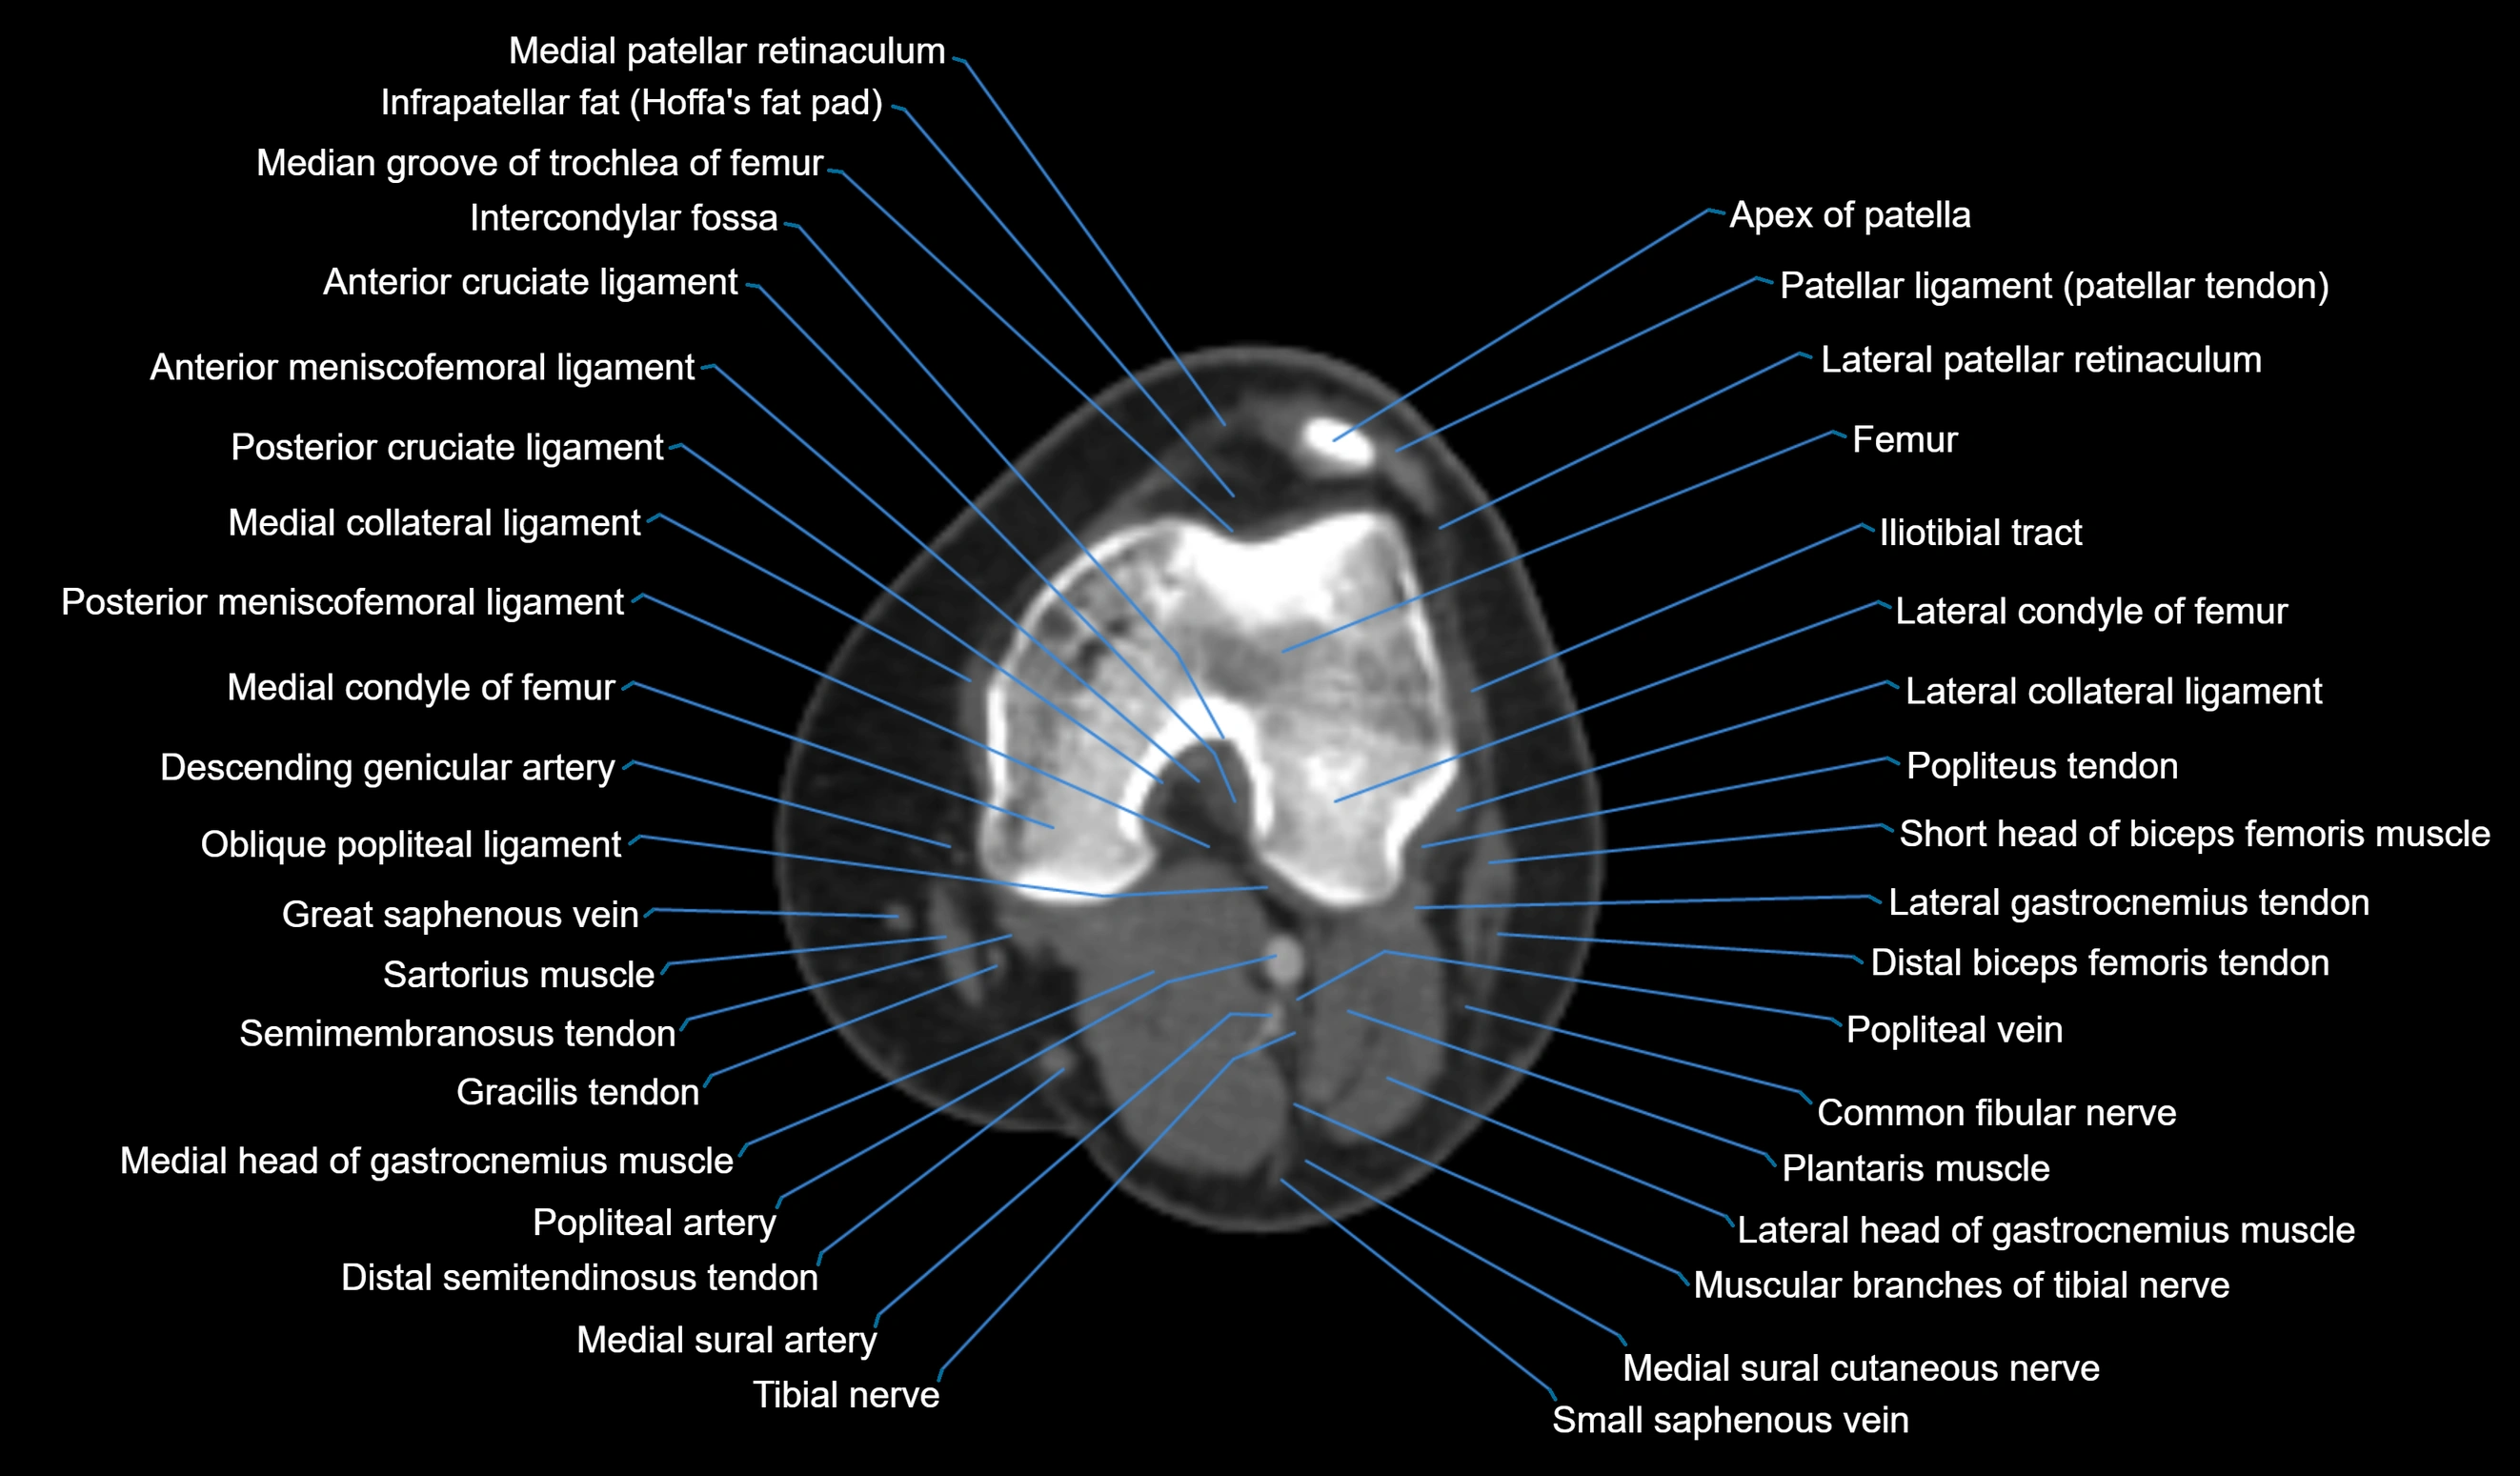

- Anterior cruciate ligament

- Anterior meniscofemoral ligament

- Common fibular nerve

- Descending genicular artery (Articular branches)

- Descending genicular artery (Saphenous branch)

- Distal biceps femoris tendon

- Distal semitendinosus tendon

- Femur

- Intercondylar fossa

- Lateral collateral ligament

- Lateral condyle of femur

- Lateral gastrocnemius tendon

- Lateral head of gastrocnemius muscle

- Medial collateral ligament

- Medial condyle of femur

- Medial head of gastrocnemius muscle

- Medial intercondylar tubercle

- Medial patellar retinaculum

- Medial sural cutaneous nerve

- Muscular branches of tibial nerve

- Oblique popliteal ligament

- Patellar tendon (patellar ligament)

- Plantaris muscle

- Popliteal artery

- Popliteal vein

- Popliteus tendon

- Posterior cruciate ligament

- Posterior meniscofemoral ligament

- Saphenous nerve

- Sartorius muscle

- Semimembranosus muscle

- Semitendinosus muscle

- Small saphenous vein

- Tibial nerve